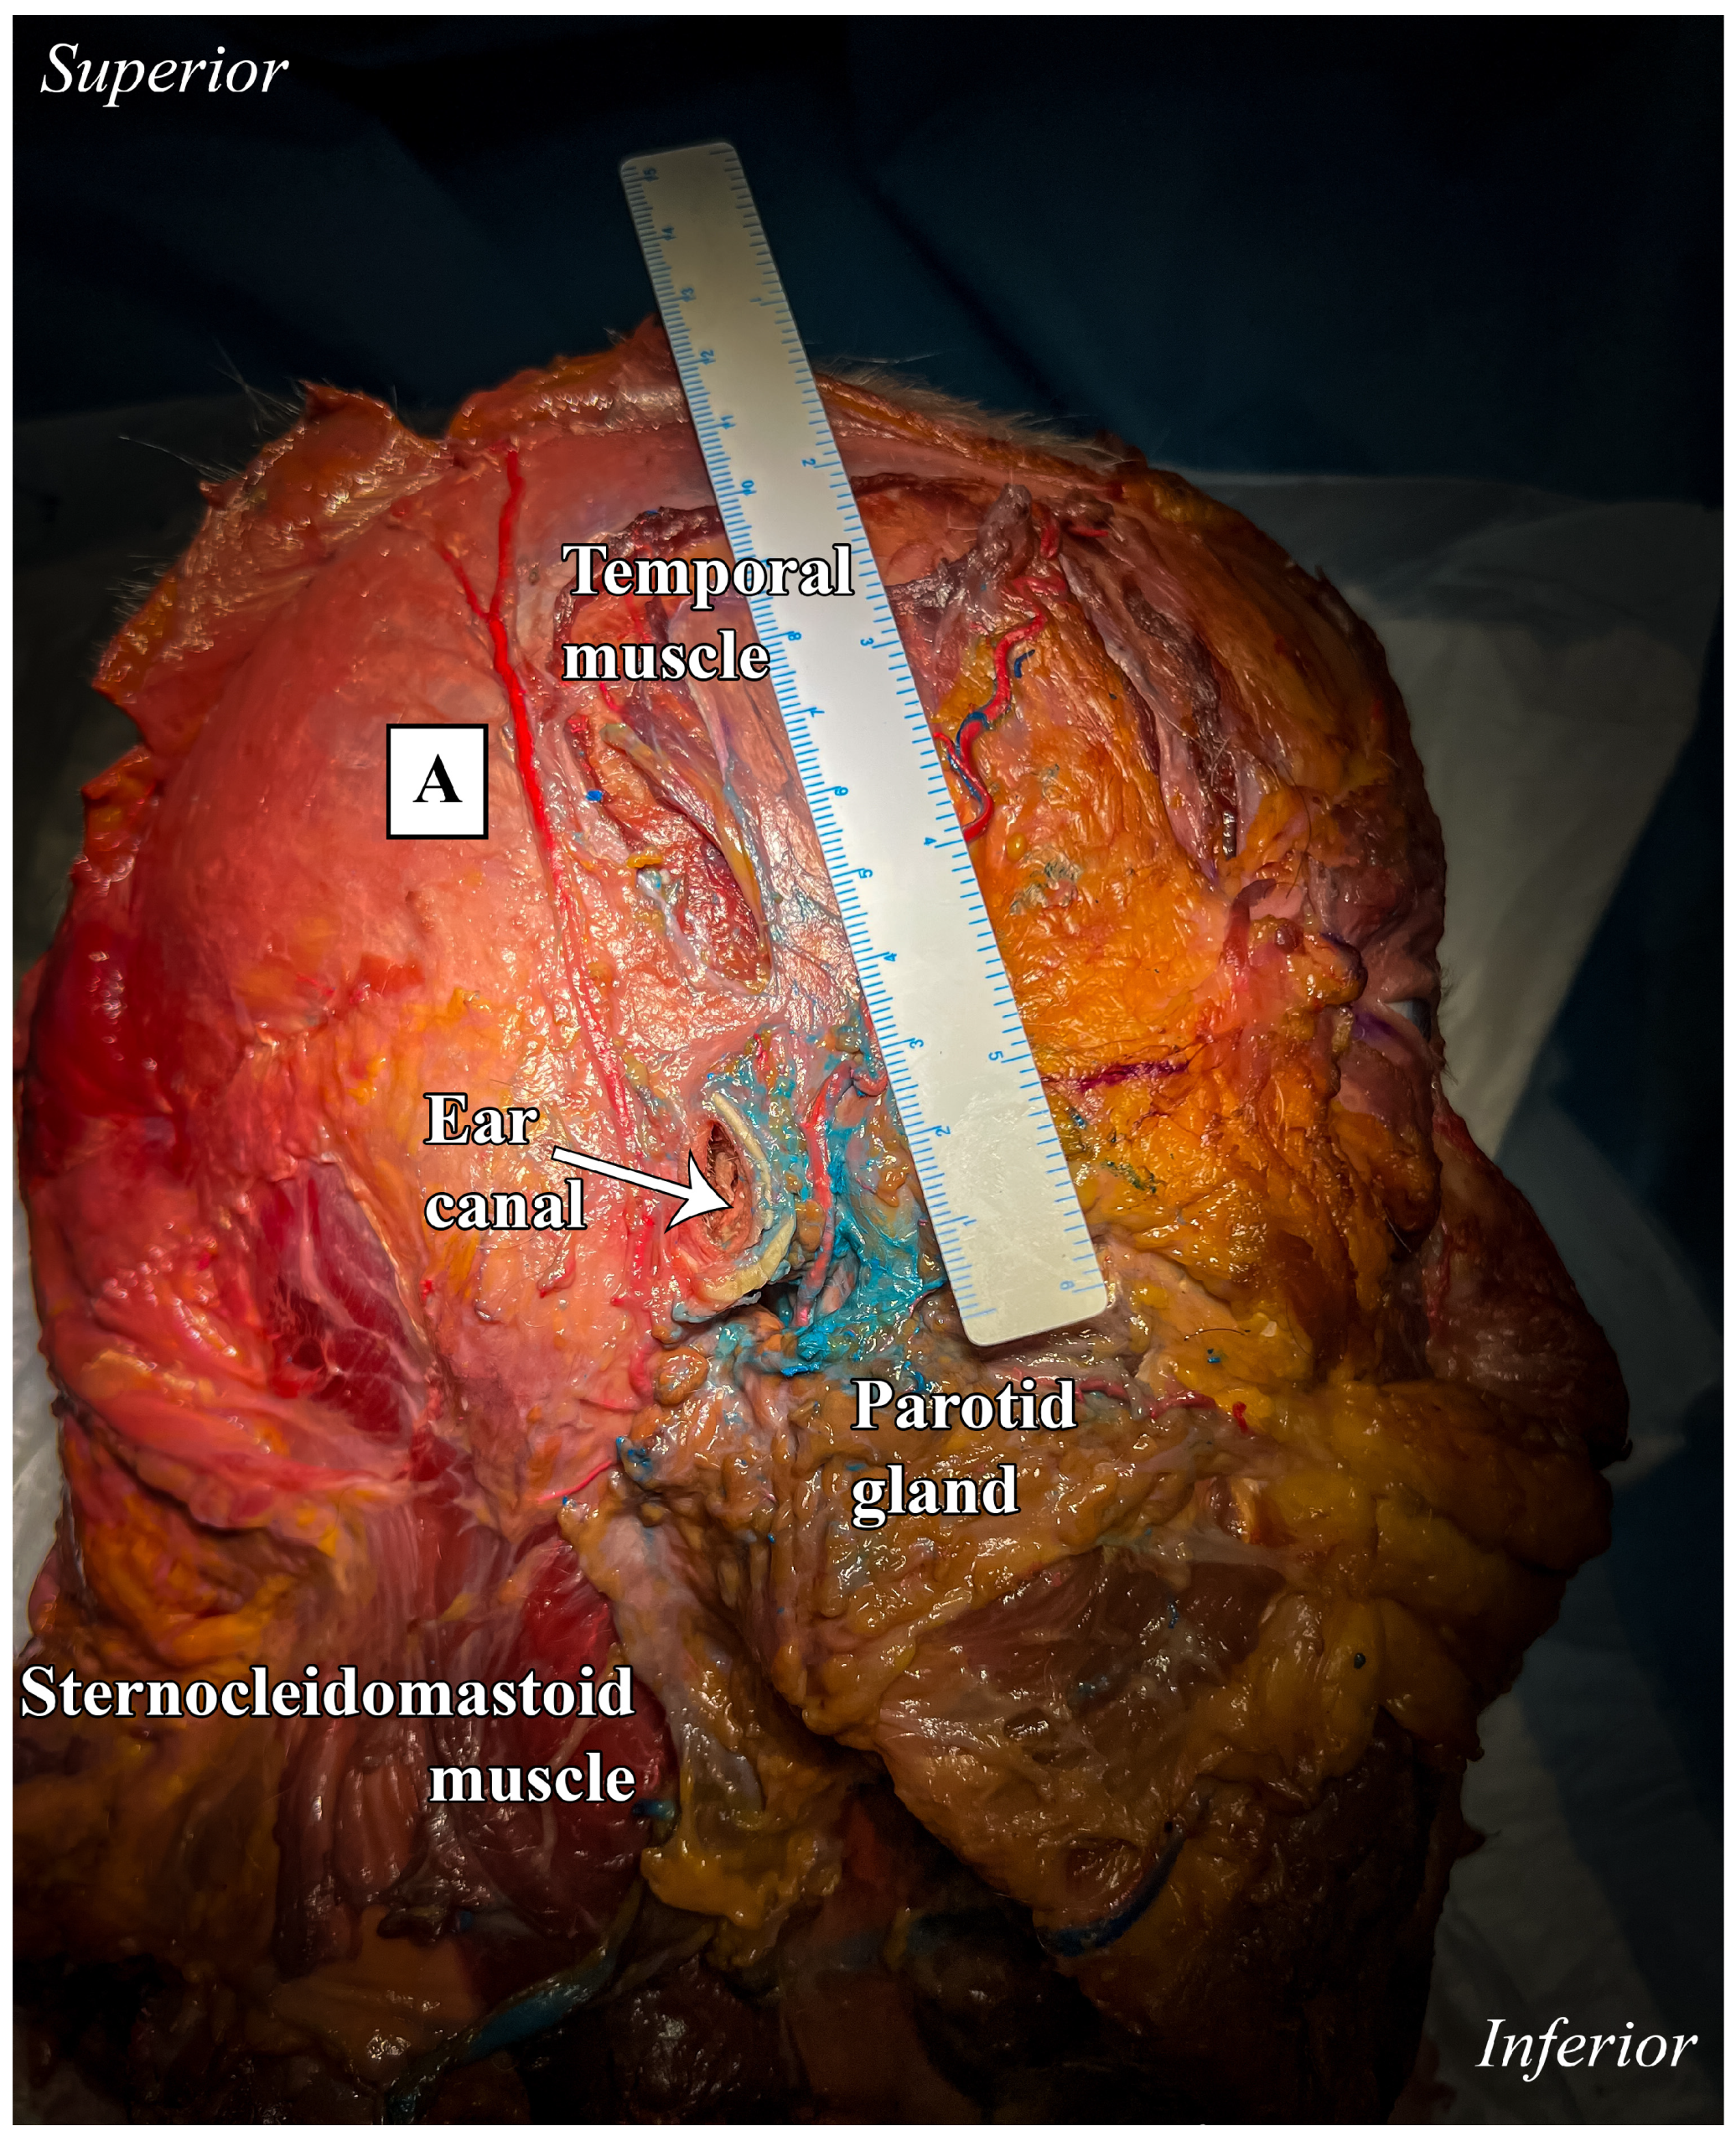

The anterior branch continued its course without further bifurcations, reaching the temporal line with a length of approximately 10 cm (Figure 4). Notably, the transverse facial artery, which typically originates from the main trunk of the STA, was in this case a collateral branch of the anterior branch of the STA (Figure 5).

Figure 4. Lateral view of anatomical preparation: temporal, infra-temporal, and parotid regions. Frontal branch (B). A ruler was used as the scale bar, providing an accurate reference for proportional measurements.